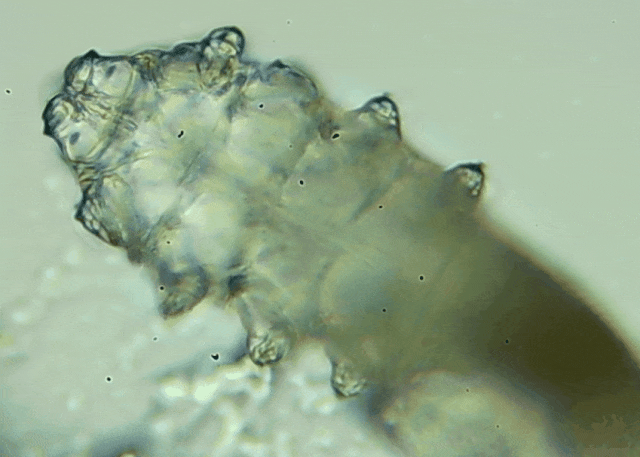

蠕形螨是一類肉眼看不見的寄生螨,常見的有毛囊蠕形螨和皮脂蠕形螨,常駐在人類的毛囊和皮脂腺里,尤其是眼睛的瞼板腺和睫毛根部。數(shù)量少時(shí),蠕形螨能與人體“和平共處”,但一旦你免疫力下降、油脂分泌旺盛或清潔不到位,他們就會(huì)以你難以想象的速度瘋狂繁殖。

而且這不是極端個(gè)案,廈門眼科中心干眼門診的臨床數(shù)據(jù)統(tǒng)計(jì),眼睛經(jīng)常紅癢發(fā)炎的人群,多數(shù)都有螨蟲,約80%以上的瞼緣炎患者螨蟲超標(biāo),一根睫毛最多能有幾十只。